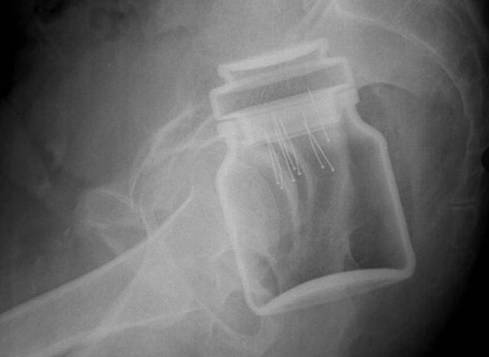

“Ci sono arance, melanzane e uova; ci sono monete, giocattoli e oggetti di uso comune come lo spazzolino da denti, ma anche contenitori insospettabili tipo barattoli vuoti e bombolette spray, strumenti interi o a pezzi come coltelli o manici d’ascia, e articoli più compromettenti come i sex toys che tradiscono un tentativo di trasgressione finito male”, spiega Gaillard, sottolineando che alcuni articoli ingoiati finiscono anche nelle vie aeree. Casi molto comuni tra i bambini.

Altri elementi piuttosto sconcertanti emergono dai raggi X del retto, testimoni di una disavventura sessuale. Tra questi molti sex toys ed altri oggetti. Casi di questo tipo, sottolinea il neuroradiologo, sono più frequenti nell’Est Europa e in Asia.

Il radiologo ha assicurato che una volta localizzati gli oggetti vengono rimossi: “Toglierli può essere una sfida, Tutto dipende dalla forma, dal materiale con cui sono fatti, dalla posizione e dall’angolazione dell’incastro”.